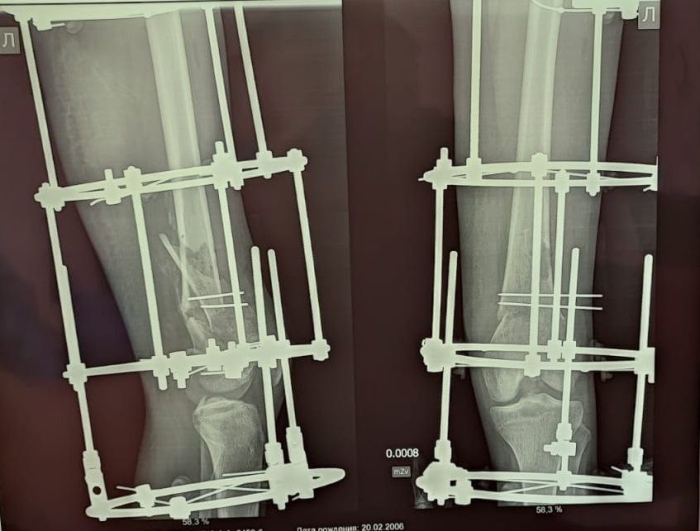

15-летняя омичка, спасаясь от пожара, выпала с 5 этажа и получила сложный оскольчатый перелом, был большой риск, что он не срастется. Девушке провели сразу две операции, собирали ногу по частям при помощи аппарата Илизарова и выполнили полиосинтез шейки бедра.

Реабилитационный период занял долгое время, но девушка соблюдала все рекомендации врачей и посещала осмотры. Сейчас аппарат Илизарова сняли и юная омичка ходит, не испытывая болезненных ощущений.

Фото: Пресс-служба министерства здравоохранения Омской области